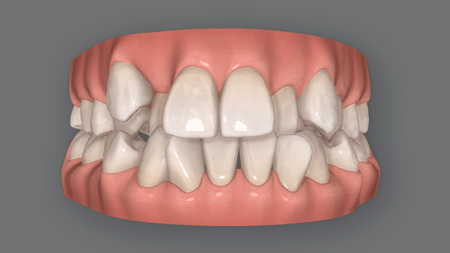

(3) 奥歯が高くて引っかかる

奥歯が引っかかって開咬

何らかの原因で奥歯が高く伸びすぎてしまうと、噛んだときに奥歯がつっかえて、前歯が閉じなくなります。

これが原因の開咬の場合、ものを噛んだ際の力が集中するため奥歯の負担が大きく、噛み合わせがおかしくなっていることが少なくありません。